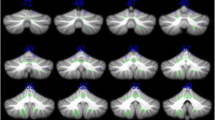

Segmentation of the caudate nucleus

Using the 3D T1-weighted image data registered to standard stereotaxic space, boundaries of the caudate volume were manually delineated (Fig. 1) by a radiologist J.H.K. using a previously published protocol (Looi et al. 2008). The radiologist was blinded as our patients and controls were anonymized and the MRI data were randomized. The caudate was outlined by drawing lines along the medial border of the internal capsule or corona radiata and along the lateral wall of the lateral ventricle. The lower margin of the head of caudate differentiating from nucleus accumbens was outlined at the most inferior slice, in which the white matter of the internal capsule separated the caudate head clearly from the putamen. The upper margin of the caudate was defined in the most superior slice in which the caudate could be seen distinct from the wall of the lateral ventricle. The tail of caudate that curved ventrally to border the lateral atrium of the lateral ventricles was not included for analysis because of difficult identification. Tracings were cross-referenced to both coronal and sagittal planes. In a week, the primary rater and another rater (H.K.) separately segmented 12 cases that were randomly selected. For these cases, we computed the Kappa statistic between the 1st and 2nd labeling of the primary rater, resulting in excellent agreement (intra-rater agreement: κ = 90 ± 1 %). Comparing between the two raters, we also found excellent inter-rater reproducibility (κ = 88 ± 2 %).

Group analysis of mean volume over all surface-points revealed bilateral global caudate volume decrease in the pmHD group compared to controls (t = 3.4; FDR = 0.005). The effect size of atrophy in the pmHD was large (Cohen’s D = 1.3; the percent of nonoverlap between groups =52 %). Point-wise analysis of local volumes mapped caudate atrophy in pmHD primarily onto medial surface (t > 2.9; FDR < 0.05), with most pronounced changes in anteromedial subdivision (Fig. 2 ; t = 4.5, FDR < 0.001 at the peak) and dorsolateral rim at the head of the caudate (t = 7.0, FDR < 0.001 at the peak). These areas showed even larger effect sizes of atrophy in the pmHD group (anteromedial subdivision: Cohen’s D = 1.8, the nonoverlap between groups =77.4 %; dorsolateral rim: Cohen’s D = 2.7, nonoverlap =82.3 %). Point-wise paired tests revealed no asymmetric atrophy in pmHD (FDR > 0.3).

Group comparison of mean caudate volume (a) and local volumes (b) between patients with pmHD and controls. Caudate atrophy was found in the pmHD group and mapped on the medial surface with the most pronounced change in the region of anteromedial subregion. Gray: non-significant / colors: significant after FDR adjustment for multiple comparisons